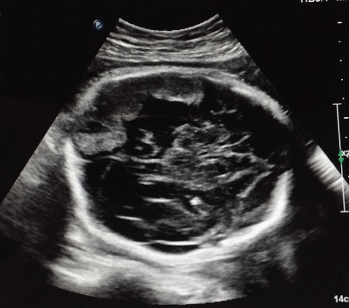

Total hospital stay in the NICU was for 8 days baby was discharged home for conservative management as an out Patient in a good neurological and general condition. A repeated CT head at the age of 2 month of age Figure 3 showed a marked interval regression of the previously seen multiple extra-axial fluid collection (sub-acute hemorrhage) with multiple area of residual 0.4 cm at the temporal 1 cm at the left parietal and 0.2 cm at the right frontal region.

Figure 3: CT head at 2 month of age, coronal view demonstrate a marked regression of the subacute hemorrhage. View Figure 3

No midline shift, no acute territorial infarction, sutures appears unremarkable with no fractures (Figure 3).